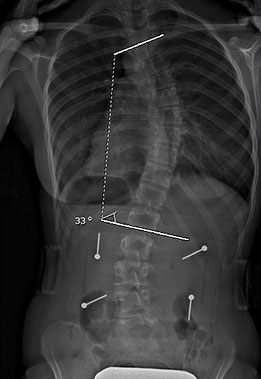

Adulte sans et avec SpineCor®

Colonne vertébrale d’une patiente scoliotique adulte, sans et avec SpineCor®

Colonne vertébrale avant SpineCor®

Colonne vertébrale avec SpineCor®

On remarque que, bien que la courbe n’ait pas changé de façon très significative, son alignement postural global est nettement amélioré par rapport à la ligne jaune centrale.